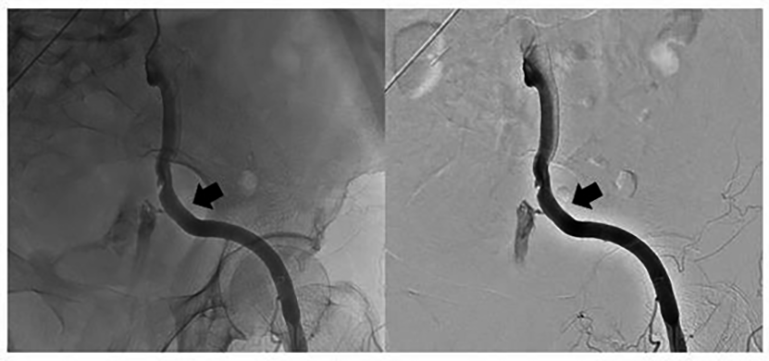

Fig. 4.Angiography showed a small source of bleeding in the upper segment of external iliac artery stent (arrow).

Emergency vascular interventional surgery was promptly performed while haemostasis and treatment of shock was administered simultaneously. The covered stent was placed rapidly in the ruptured external iliac artery pseudoaneursm to block the bleeding source and it also ensured blood supply to the lower limbs. However, it should be noted that she needed to undergo a second interventional surgery 5 hours later. This could have been related to leakage of the covered stent or increased blood pressure and vasodilation. Moreover, clinicians should be alert to complications such as stent obstruction, deformation and kinking, stent loss, intimal hyperplasia and infection after placement [24]. However, no such complications were observed in the patient during follow-up.